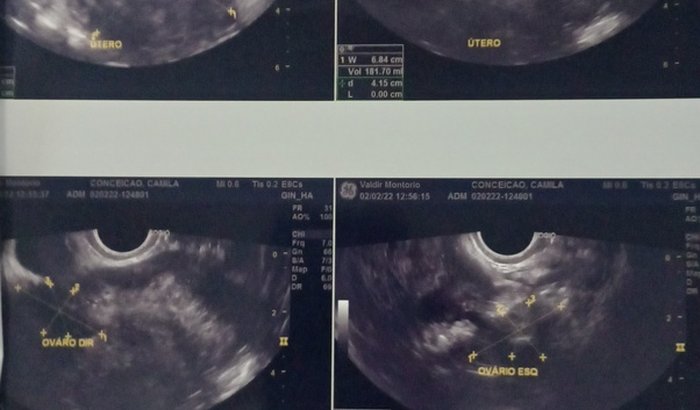

Boa noite eu me chamo Camila Rodrigues da Silva Conceição eu tenho 32 anos em 2017 descobri eu tenho mioma no útero não consigo engravidar preciso de ajuda pra mim conseguir engravidar por caso do mioma preciso de uma cirurgia urgente por favor se vcs puderem me ajudar meu sonho é ser mãe por causa do mioma eu não consigo pelo amor deus me ajuda por favor eu não tenho condições pra acar com a cirurgia Por favor se vcs me puderem me ajudar sua ajudar de vcs vai ser bem vinda